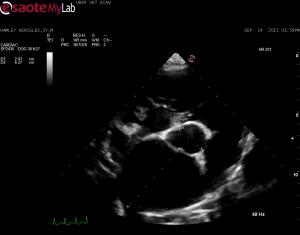

– echo shows LV and RV dilation, severe LAE

– poor systolic function with increased LVIDs; FS 14-18%

– moderate TR and moderate- severe MR; aortic and pulmonic max velocities wnl

Look how flattened the IVS is in this dog. R ventricular pressures must be pretty highn